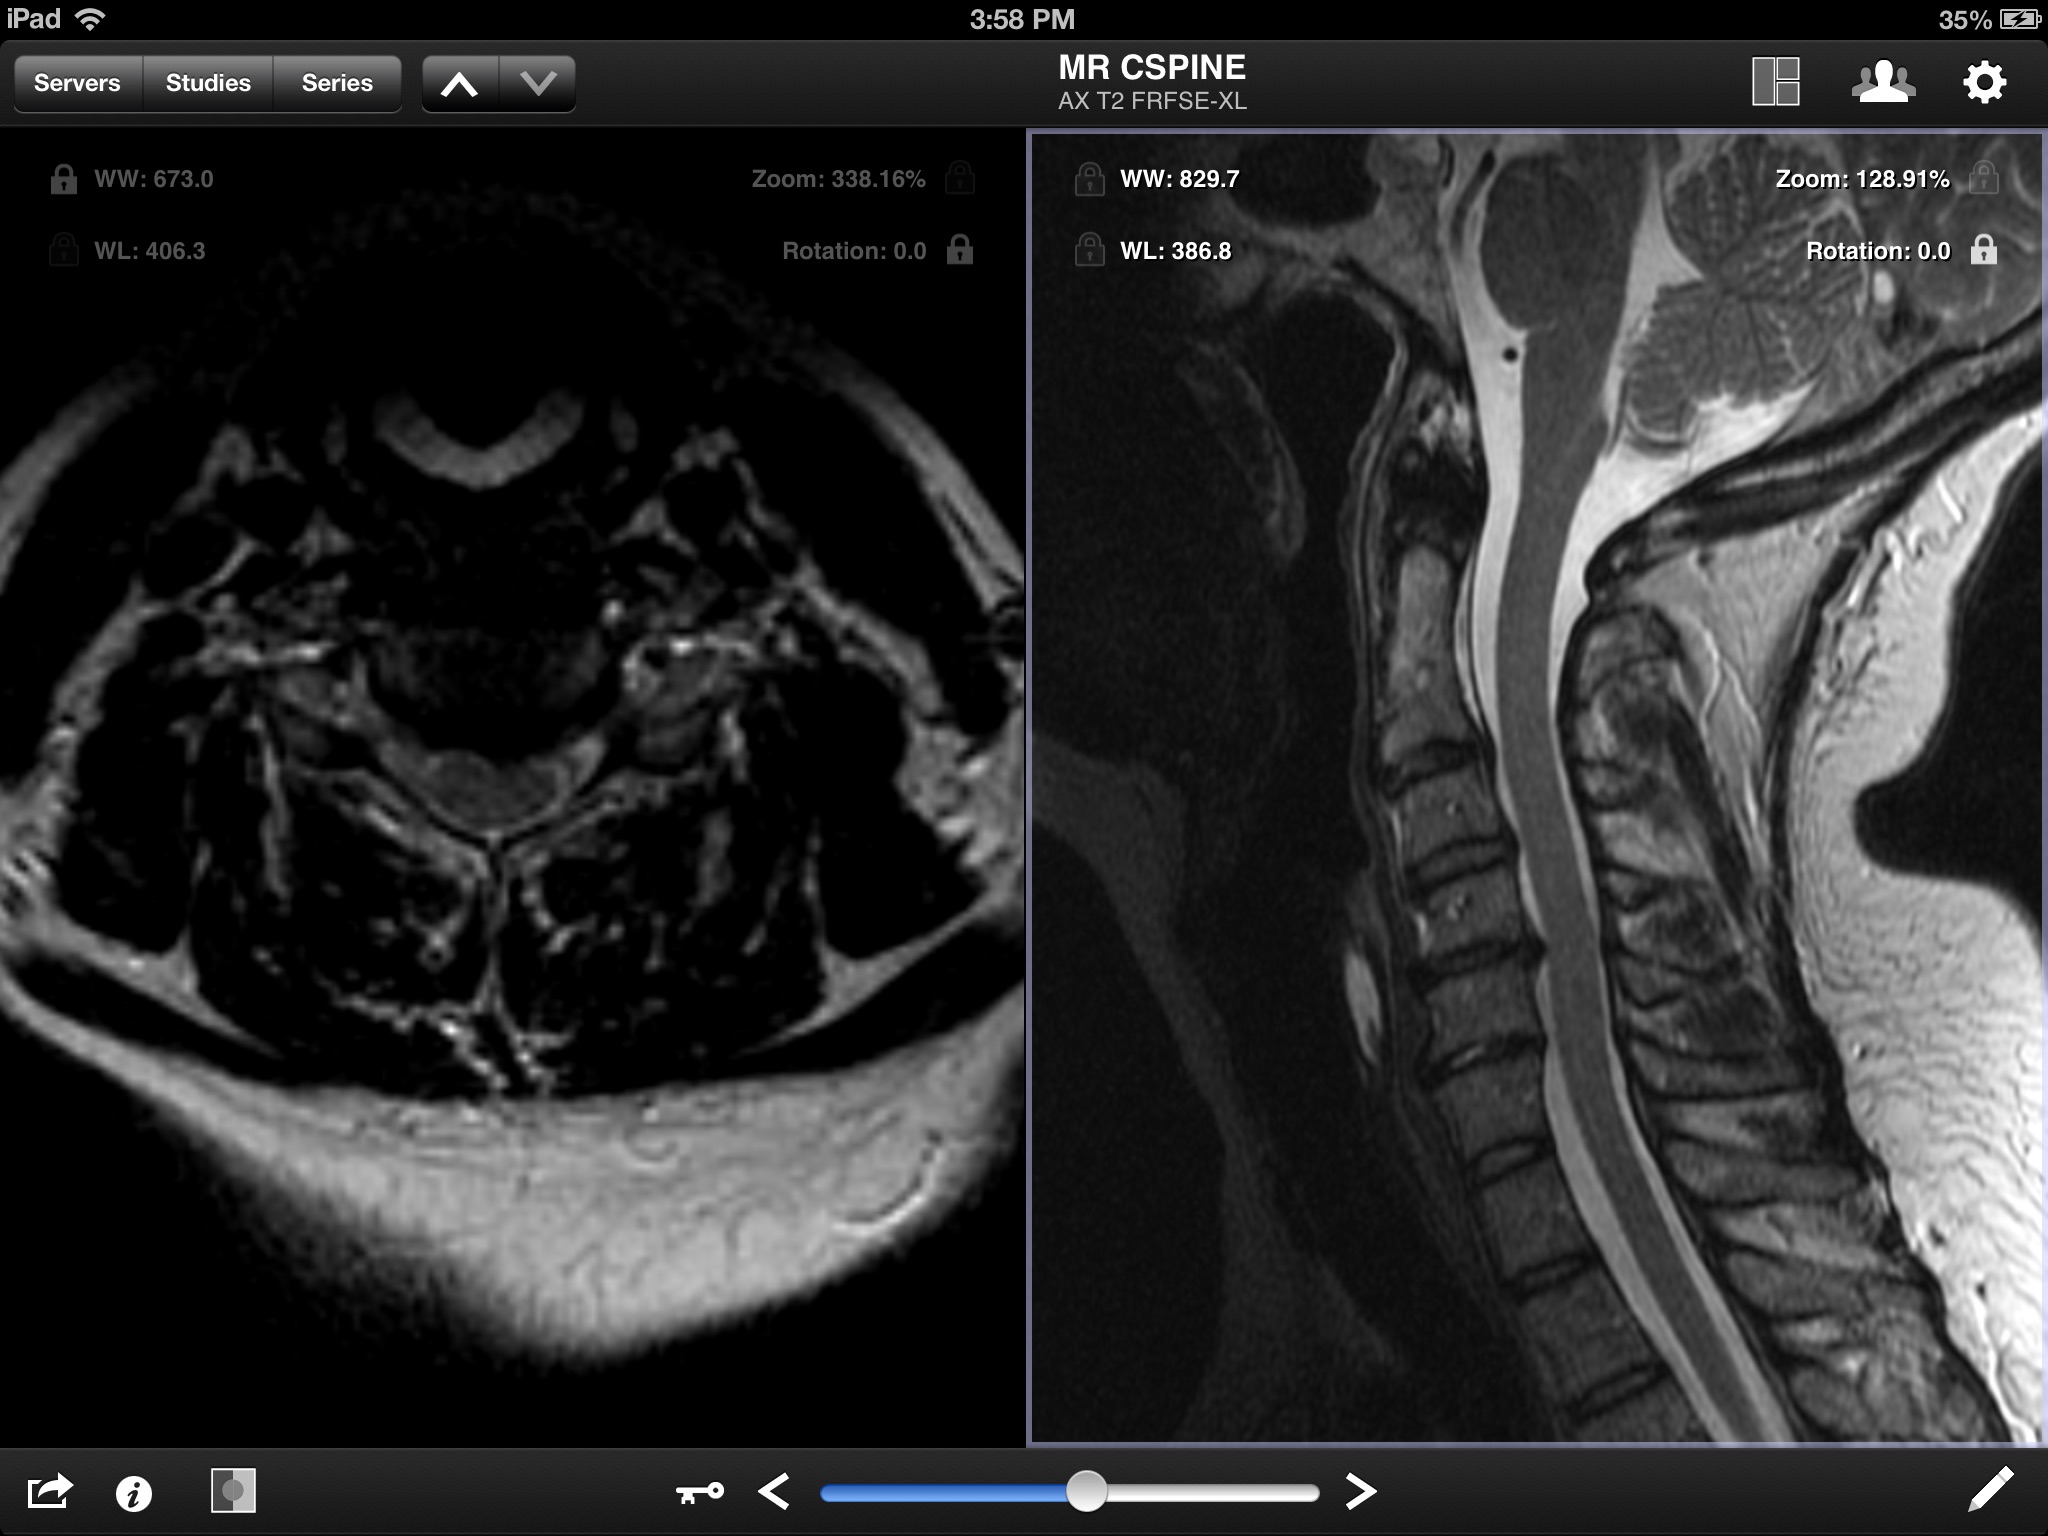

Jack Imaging Medical Image Viewer, a medical image viewer for the iPad, is the latest in medical imaging innovation! It supports reading the DICOM format ( the industry standard for storing medical images) and the most common imaging modalities. Jack Imaging Medical Image Viewer supports fast user interaction for the most common actions, including zoom, pan, windowing (brightness and contrast adjustment) using multitouch gestures.

- View DICOM images

- View transformation (zoom, pan) using two finger multi-touch

- Adjust window width & level using one finger drag

- Full image resolution. Images will NOT be scaled down to 1024x1024 only.

- View the full image intensity window.

- Full GPU optimized rendering. Window operations are FAST and responsive.